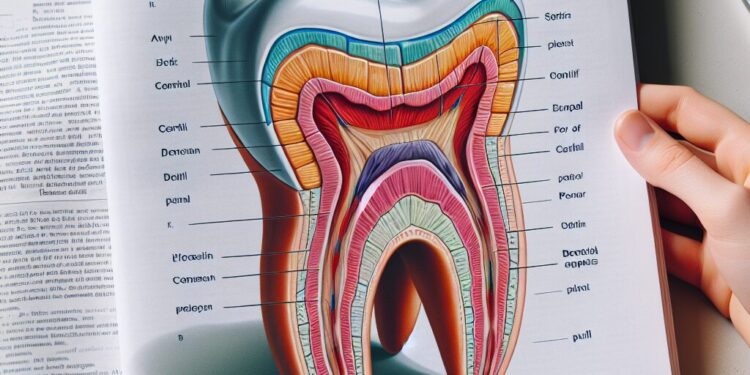

A anatomia do dente é um tema fundamental para compreender não apenas a estrutura dos nossos dentes, mas também seu funcionamento e importância para a saúde bucal como um todo. Cada dente possui características específicas que garantem seu papel na mastigação, fala e estética, sendo composto por várias partes que trabalham em conjunto para manter sua integridade e funcionalidade.

O dente é formado por estruturas principais que podem ser divididas em três partes básicas: coroa, colo e raiz.

Coroa: É a parte visível do dente na boca, coberta pelo esmalte, a substância mais dura do corpo humano. A coroa é responsável pelo contato direto com os alimentos durante a mastigação.

Colo: Região de transição entre a coroa e a raiz. É onde o dente se estreita e fica mais próximo à gengiva.

Raiz: Parte que fica inserida no osso alveolar, presa por meio do ligamento periodontal. Ela mantém o dente fixo e suporta as forças provocadas pela mastigação.

Camadas do dente

O dente é composto por três camadas principais, cada uma com uma função distinta e estrutura química específica:

Esmalte: É a camada mais externa que cobre a coroa dentária, formada predominantemente por minerais, especialmente hidroxiapatita, que confere alta resistência e proteção contra o desgaste e agentes externos. Por ser avascular, o esmalte não possui células vivas e não se regenera após danos.

Dentina: Localizada logo abaixo do esmalte e do cemento, a dentina é uma camada menos mineralizada e mais porosa, composta por túbulos dentinários que permitem a condução de estímulos ao interior do dente. É responsável por fornecer suporte estrutural ao esmalte e transmitir sensações dolorosas ou térmicas.

Polpa dentária: O tecido mais interno do dente, repleto de nervos, vasos sanguíneos e células conjuntivas. A polpa é vital para a nutrição e sensibilidade do dente, estando localizada na câmara pulpar da coroa e nos canais radiculares na raiz.

Cemento e ligamento periodontal

Além das camadas internas, o dente possui uma cobertura chamada cemento, que reveste a raiz e ajuda na fixação do dente ao osso alveolar. Esse tecido mineralizado é semelhante ao osso, porém menos rígido que o esmalte.